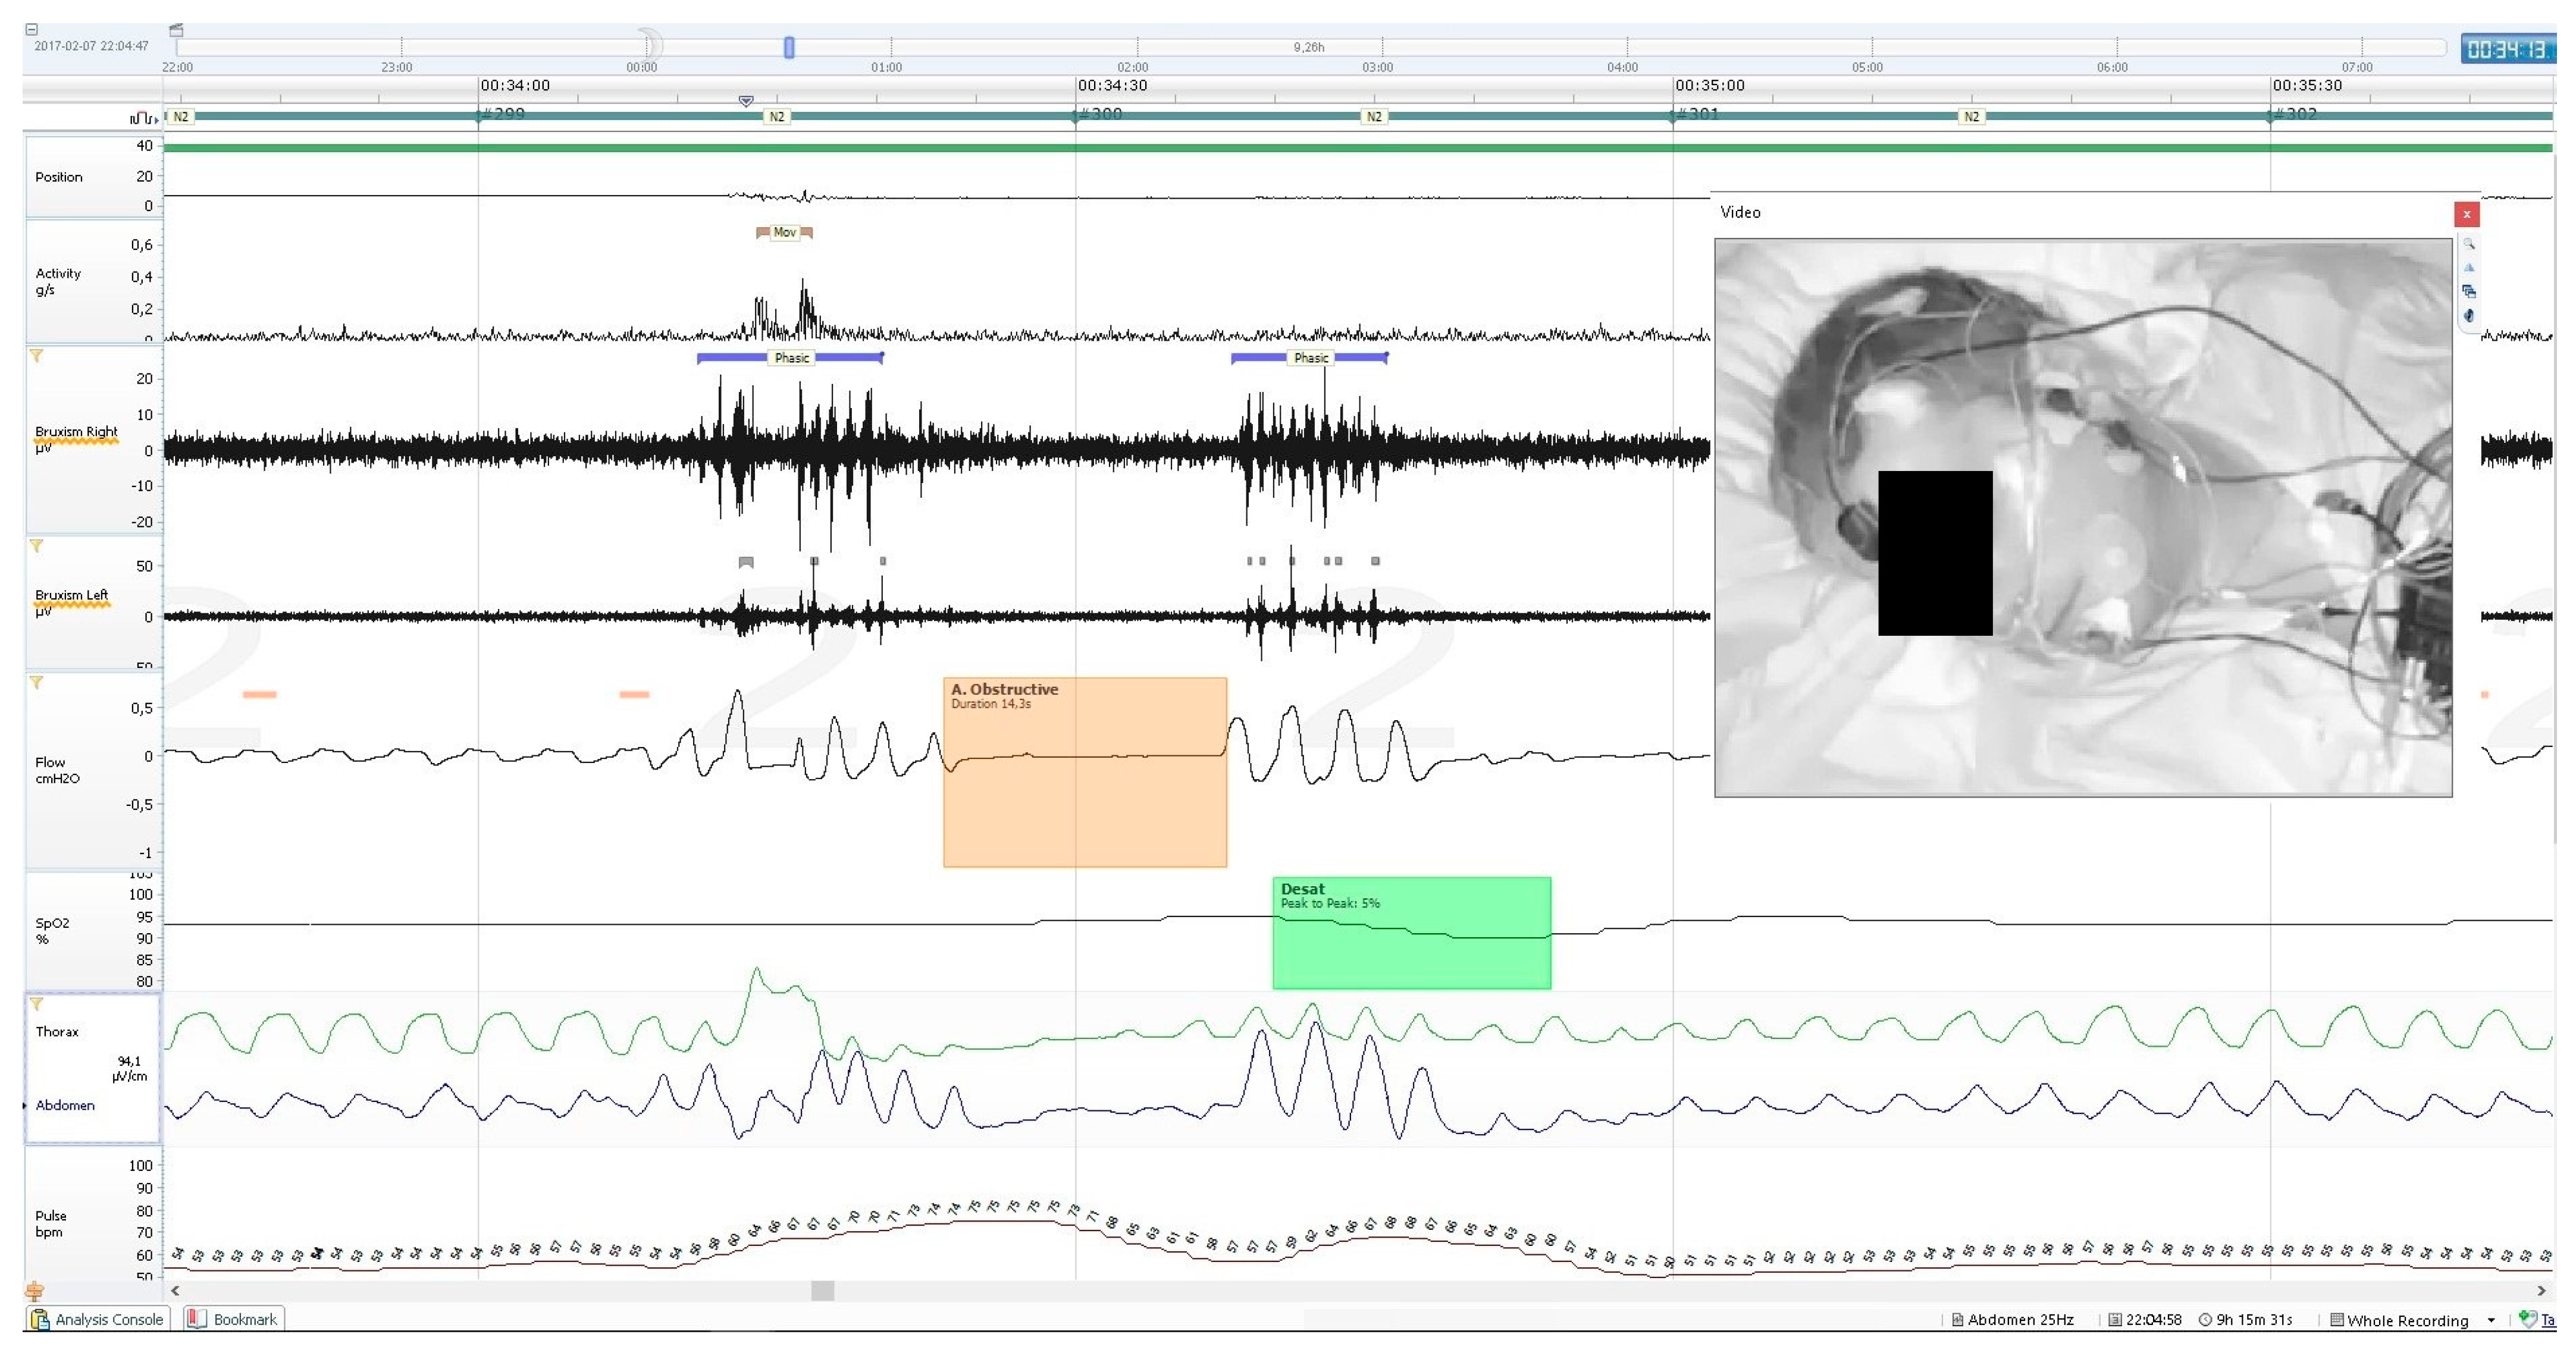

Activity parameters were measured along with whole-night PSG recording, using the built-in sensor of the central unit of the mobile PSG device (Nox A1). It records 3-axis gravity signals with a range of −1 to 1 times of Earth’s gravity units (g). The axes were positioned in such a way that the x-axis goes through the chest, the y-axis goes from shoulder to shoulder, and the z-axis goes from the feet to the head. From these signals, the angle of rotation was measured from the arc tangent of y and x. The acceleration signal was used to derive the position signal measured in a 360°scale and the activity signal measured in g/s. The device supports a 20 Hz sampling rate of the activity signals with a noise level of <20 mGRMS on each axis. The activity signal was calculated from raw gravity signals measured using an accelerometer in the recording device, where it was the absolute change of the length of the x- and y-axis vectors. The z-axis, which runs parallel to the patient’s body, did not contribute relevant information and was therefore omitted from the calculation. An example of PSG recording with a marked MA episode is presented on Figure 1. The following activity parameters were recorded and calculated:

Figure 1. An example of PSG recording, showing a single short MA episode (the uppermost channel), two episodes of phasic bruxism (marked with a purple strip, shown on two widest black canals—registration of the masseter muscle EMG), an episode of obstructive apnoea separating two bruxism episodes (marked with an orange box on the air flow chart) and a desaturation episode following the apnoea (marked with the green box on the pulse oximetry channel). This MA episode occurred within the first phasic bruxism episode, it was a short movement of head, neck and whole body without any change of body position.